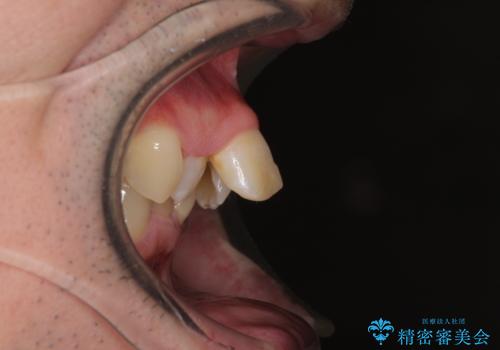

- ぶつけて前歯が折れてしまったとのことで来院された患者様です。

折れてしまった前歯は軽傷であり、歯内の歯髄に影響は及んでいませんでした。

通常では速やかにオールセラミッククラウンにて補綴治療を行うのですが、デコボコしている歯列も気になっていたため、事前に矯正治療を行うこととしました。